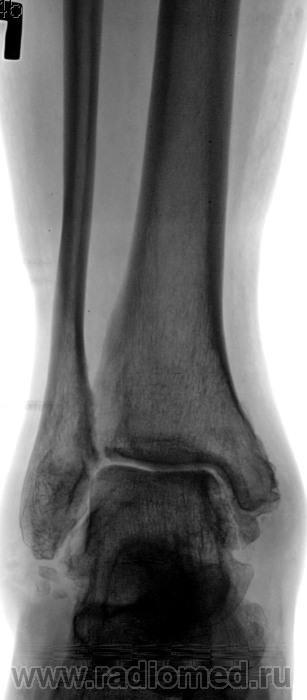

Переломы костей голени (большеберцовой и малоберцовой) и костей заднего отдела стопы (таранной и пяточной) приводят к возникновению деформирующего артроза голеностопного и подтаранного суставов. Это заболевание возникает также вследствие дегенеративно-дистрофических изменений, вызванных ревматическими и неврологическими болезнями, пожилым возрастом пациента.

Деформирующий посттравматический артроз голеностопного сустава

Голеностопный сустав — сложная биомеханическая структура. В его состав входит наружная (латеральная) лодыжка, внутренняя (медиальная) лодыжка, таранная кость, большеберцовая кость, многочисленные связки.

В большинстве случаев деформирующий артроз является следствием перенесённой тяжёлой травмы одной или нескольких его анатомических составляющих — наружной и внутренней лодыжки, большеберцовой кости, таранной кости. В результате травмы поверхность костей, входящих в сустав, становиться неровной, что приводит к нарушению скольжения суставных поверхностей и их дополнительной травматизации при движении.

При диагностике остеоартрита хирург стопы и голеностопного сустава тщательно осматривает стопу на предмет припухлости в суставе, ограничения подвижности и боли при движении.

В некоторых случаях может отмечаться деформация и/или увеличение (шпора) сустава. Для оценки степени заболевания может быть назначен рентген.